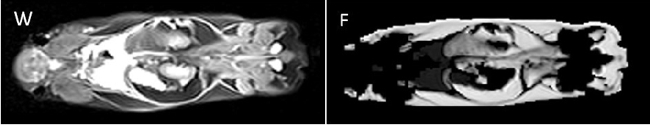

b) Small Animal MRI

Christian Kremser

In addition to clinically oriented projects, the Department of Radiology conducts experimental MR examinations on various animal models and specimens. Over the years, coil setup and imaging sequences have been optimised accordingly. Study topics include: mouse spinal cord imaging after shock wave treatment to promote spinal cord repair; volumetry of mouse myocardium to quantify fibrotic changes after constriction of the aorta and pulmonary artery; volumetry of the mouse brain to quantify fixation shrinkage; pulse wave velocity imaging in rabbits to evaluate aortic plaques; volumetric quantification of subcutaneous and visceral fat in mice on different diets; detection of intervertebral disc herniation in knockout mice.